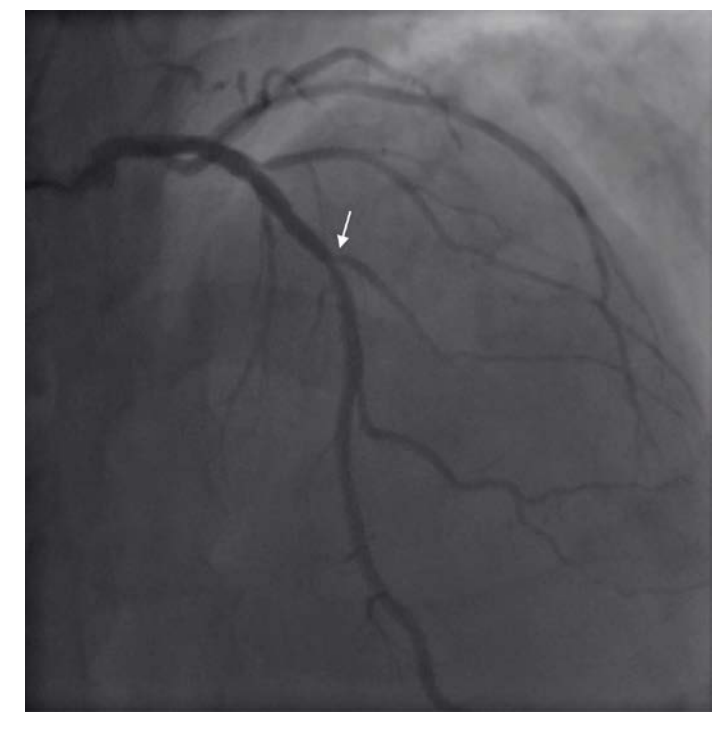

Coronary angiography (CA) was performed 24 hours after admission, an intermediate stenosis was found in the left anterior descending artery (LAD) with TIMI 3 flow (Figure 2). Ventriculography showed mild anteroseptal hypokinesia with a 60% left ventricular ejection fraction (LVEF). Aortic root dilation was observed along with a double contour image suggestive of aortic dissection (Figure 3). Aortic CT was then performed, the study revealed an aortic dissection extending through the thoracic, abdominal and common iliac arteries, classified as a Type A aortic dissection (Figures 4-6). CT angiography 3D reconstruction showed a dissection originating at the aortic root that involved the innominate, left subclavian and left vertebral arteries as well as the descending aorta and extended through the entire course of the common iliac artery causing left iliac artery occlusion (Figure 7).